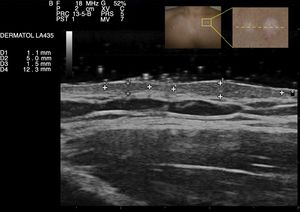

Se realizó una ecografía de alta frecuencia (18MHz, Esaote® MyLabTM25Gold) de 2 lesiones contiguas en la que se evidenciaron 2 zonas focales ovaladas de engrosamiento y disminución de la ecogenicidad dérmica, de aspecto sólido y que solevantan la epidermis. El plano dérmico superficial entre las 2 zonas focales no mostraba alteraciones ecográficas (fig. 2). Estas lesiones no captaban flujo vascular en el estudio con Doppler color. La ecoestructura de las otras lesiones era similar a la descrita.

Los hallazgos ecográficos de esta entidad son inespecíficos, debiendo hacer el diagnóstico diferencial con otros tumores de partes blandas con semejanzas clínicas y ecográficas, como los dermatofibromas, el granuloma anular, los piloleiomiomas múltiples o los queloides espontáneos, entre otros. A veces podemos encontrar características diferenciales que nos pueden orientar hacia un diagnóstico, como las líneas hipoecoicas periféricas en los dermatofibromas o el patrón lineal fibrilar hiperecogénico en los queloides. No obstante, a menudo precisaremos de la información histopatológica para alcanzar el diagnóstico definitivo.